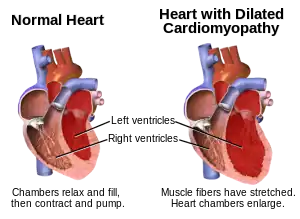

| Dilated cardiomyopathy | |

Dilated cardiomyopathy (DCM) is a condition in which the heart becomes enlarged and cannot pump blood effectively.[3] Symptoms vary from none to feeling tired, leg swelling, and shortness of breath.[2] It may also result in chest pain or fainting.[2] Complications can include heart failure, heart valve disease, or an irregular heartbeat.[3][4]

The progression of heart failure is associated with left ventricular remodeling, which manifests as gradual increases in left ventricular end-diastolic and end-systolic volumes, wall thinning, and a change in chamber geometry to a more spherical, less elongated shape. This process is usually associated with a continuous decline in ejection fraction. The concept of cardiac remodeling was initially developed to describe changes that occur in the days and months following myocardial infarction.[26]

The above model reveals a gradual dilation of the myocardium, especially the ventricular myocardium, to support the blood volume overload in the chambers. Dilation manifests itself in an increase in total cardiac mass and cardiac diameter. Cardiomyocytes reach their maximum length of 150 m in the endocardium and 130 m in the epicardium by the addition of sarcomeres.[27] Due to the increase in diameter, the dilated heart appears spherical in shape, as opposed the elliptical shape of a healthy human heart. In addition, the ventricular walls maintain the same thickness, characteristic of pathophysiological cardiac dilation.